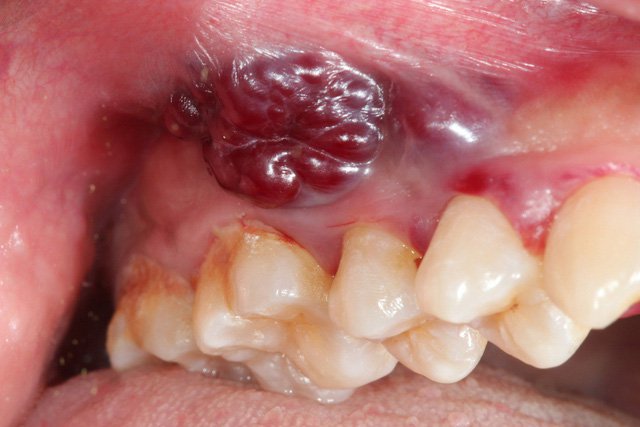

Ung thư khoang miệng là một loại ung thư ác tính xuất hiện tại vùng khoang miệng bao gồm: lưỡi, lợi hàm dưới, niêm mạc má, sàn miệng, lợi hàm trên.

Các triệu chứng của ung thư khoang miệng bao gồm: vết loét bên trong má hoặc môi không lành, có thể sờ thấy một cục u hoặc mảng màu đỏ trắng trong miệng, răng hoặc răng giả có thể bị lung lay mà không rõ lý do, miệng xuất hiện các vết loét giống nhiệt miệng nhưng kéo dài hơn 2 tuần không khỏi, gây nóng rát, đau đớn trong miệng, vận động lưỡi và tri giác kém, lưỡi bị tê và mất cảm giác, chảy máu khoang miệng.